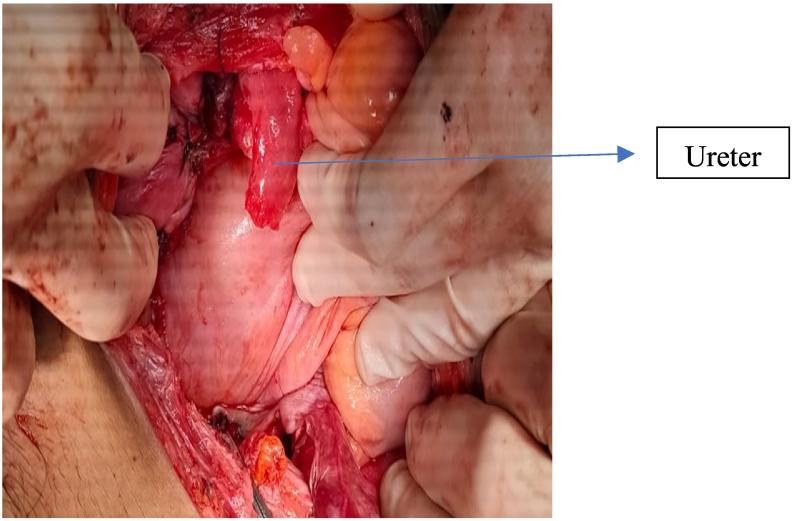

We present the case of ureter injury during subtotal hysterectomy in patient with PAS. A 30-years-old female patient was diagnosed with recurrent antepartum hemorrhage due to placenta previa accreta spectrum on G2P1 33 weeks of gestational age, singleton live breech presentation, previous c-section 1×. After uterine transverse incision, the baby was delivered. We decided to perform subtotal hysterectomy. There was severe adhesion. On the exploration after subtotal hysterectomy was performed, we found ruptured of the right ureter.

我们报告一例PAS患者在次全子宫切除术中发生输尿管损伤的病例。一名30岁女性患者,孕2产1,孕33周,单胎臀位,既往剖宫产1次,因前置胎盘植入谱系疾病诊断为复发性产前出血。子宫横切口后,娩出胎儿。我们决定行次全子宫切除术。粘连严重。次全子宫切除术后探查发现右侧输尿管破裂。